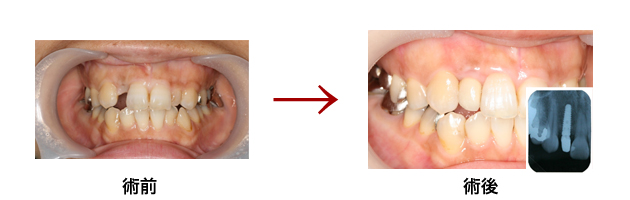

症例集

天然の歯と同様の機能と審美性